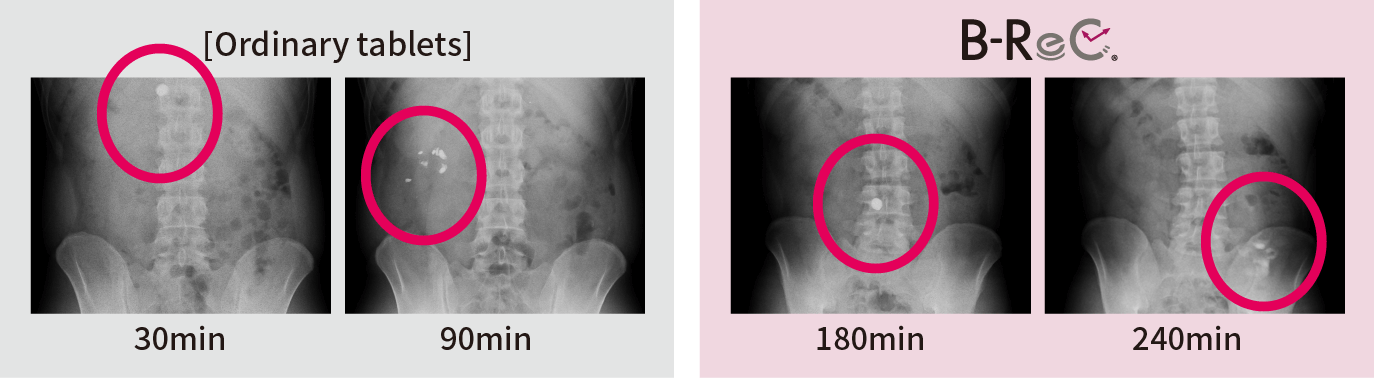

We confirmed the pharmacokinetic profile of ordinary tablets and B-ReC tablets. Ordinary tablets completely disintegrated within 90 minutes from the stomach to the duodenum, but the jejunum-disintegrating B-ReC tablets did not disintegrate in the upper small intestine (jejunum) even 180 minutes after ingestion, but in the middle small intestine after 240 minutes.

This proves that

the formulation can deliver the

functional ingredients

to the target site in the

digestive tract. -